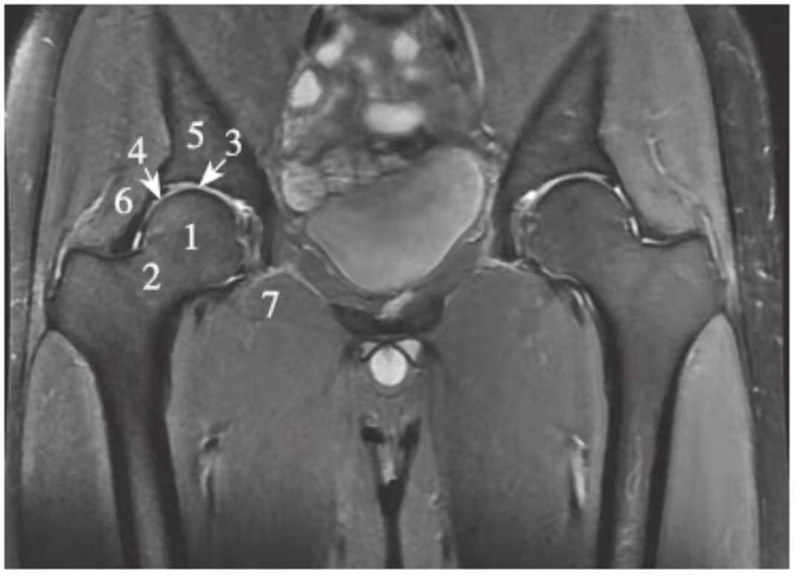

正常髋关节经股骨头中心层面T2WI抑脂像

1.髂骨;2.股骨头;3.股骨头凹;4.股骨颈;5.大转子

正常髋关节经股骨头中心层面PDWI抑脂像

1.股骨头;2.股骨颈;3.关节软骨;4.髋臼盂唇;5.髂骨;6.臀小肌;7.闭孔外肌